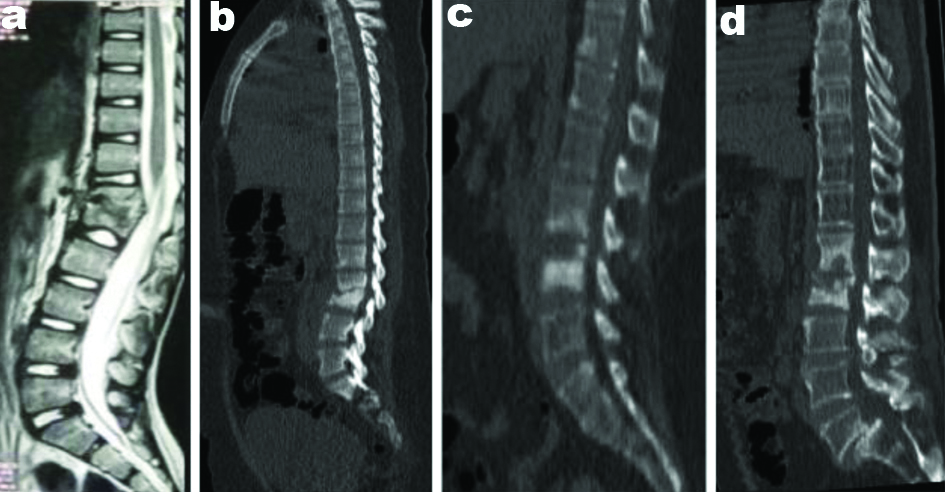

The preoperative images of the spine of all the four cases has been represented in [Table/Fig-1(a-d)]. And postoperative images of radiographic of all cases are shown in [Table/Fig-2(a-d)].

Mid sagittal of whole spine.

a. Case 1: T2 weighted MRI image showing D11-D12 vertebral body destruction.

b. Case 2: CT scan showing destruction of L2-L3 with local kyphosis.

c. CT scan showing spondylodiscitis of L3-L4.

d. Case 4: CT scan showing L1-L2 spondylodiscitis

Routine diagnostic parameters were within normal limits except Erythrocyte Sedimentation Rate (ESR) which was 96 mm/hour. MRI brain image showed multiple nodular lesions in the supra and infratentorial brain and brainstem. Likewise, the MRI of the spine revealed D11-D12 vertebral body destruction with anterior vertebral body collection [Table/Fig-1a]. The tentative clinical diagnosis recorded was TB granuloma of the brain lesions and TB abscess of spine lesions.

On examination, central tenderness over the lumbar spine extending from L1-L4 was present associated with an increase in paraspinal muscle tone. No sinus or scar was seen. Routine diagnostic parameters were within normal limits except ESR was 44 mm/hour. Mantoux test showed 18 mm induration after 48 hours. CT scan showed destruction of L2 and L3 vertebral bodies [Table/Fig-1b] with bilateral psoas abscess.

On examination, tenderness was present at L2-L3 vertebrae with a spasm of paraspinal muscles. Routine diagnostic parameters were within normal limits except ESR was 90 mm/hour. Mantoux test showed 21 mm induration after 48 hours. CT scan showed lumbar spondylosis with spondylodiscitis of L3-L4 [Table/Fig-1c].

A 62-year-old male, with diabetes mellitus and Ischaemic Heart Disease (IHD), presented with low backache for three months, insidious on onset, progressive and radiating to both the lower limbs for the last 10-12 days. The patient had undergone radical subtotal gastrectomy and jejunostomy in 2017 and underwent chemotherapy and radiotherapy following surgery. The patient was admitted on and off with a history of low back pain. Relevant investigations were done and were within normal limits except ESR was 140 mm/hour. On examination, tenderness present over L1–S1 vertebrae with paraspinal tenderness. CT scan showed features suggestive of spondylodiscitis at L1-L2 [Table/Fig-1d] with postoperative status with grade 2 spondylolisthesis of L5 over S1 with L5 bilateral spondylolysis.